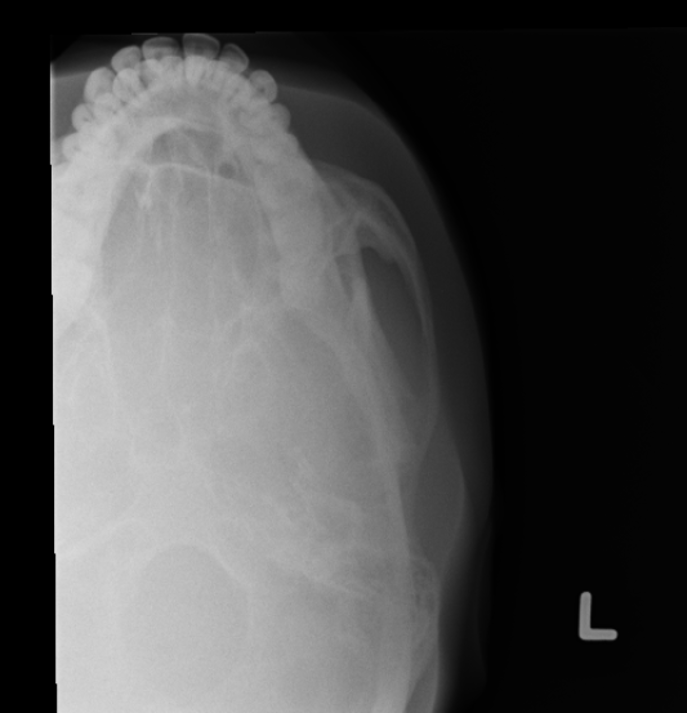

AP axial of skull - Towne method

AP axial skull - Towne method